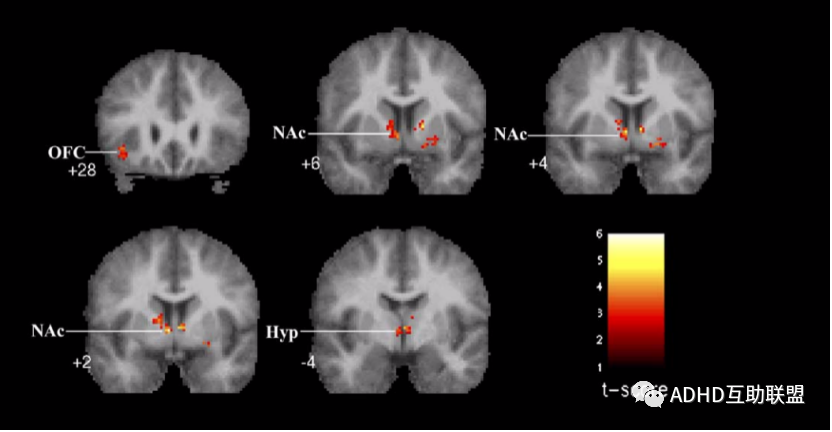

1.目前多认为多巴胺(DA)的功能不足是 ADHD 主要发病机制之一,功能磁共振研究发现,音乐可强烈激活伏隔核(NAC)、腹侧被盖区(VTA)和下丘脑、脑岛,伏隔核和腹侧被盖区的激活会帮助多巴胺的释放,从而改善ADHD儿童的核心症状。

研究发现,和听杂乱的音乐相比,志愿者在听古典音乐时,大脑伏隔核和包括腹侧被盖区、下丘脑和眶额叶在内的相关中脑边缘结的大脑网络被激活(伏隔核和大脑奖赏系统有关)。这些脑区负责奖赏、自我管理和认知处理。

(和听杂乱的音乐相比,志愿者在听古典音乐时,伏隔核和包括腹侧被盖区、下丘脑和眶额叶在内的相关中脑边缘结构的大脑网络被激活。)